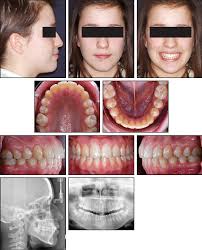

In such a case a closed eruption technique would provide both teeth a vital state. Interventions for promoting the eruption of palatally displaced permanent. 26,27 in the case shown here, closed eruption was chosen for the impacted central and. Within the different approaches there exist two main options for the subsequent eruption of the impacted teeth (6): Despite the unconcealed allocation, the outcome duration of canine's eruption is probably in low risk of bias as the protocol of open and closed technique is mentioned clearly, any possible confounders (age, depth of impaction) have similar distribution at baseline among groups and the definition of eruption is objective.

Natural autonomous eruption and forced eruption under orthodontic traction. Postoperative pain experienced by patients was similar, but regression of pain was faster in closed eruption technique. Forced eruption can preserve the natural root system and related periodontal architecture, resulting in years of additional service for the patient. It also can maintain adjacent tooth structure while retaining the option for future implant reconstruction. The postoperative recovery was longer after open eruption than close eruption technique (p = 0.000). 26,27 in the case shown here, closed eruption was chosen for the impacted central and. Dr vanarsdall recommends open exposure with a repositioned gingival flap (pediculated connective tissue graft) above the impacted canine. Management of unerupted maxillary incisors 6 5.4 incisor removal 5.5 ankylosed maxillary incisors.

This facilitates eruption and orthodontic traction. The difference in time required for the two techniques was statically significant (p = 0.000). 5.3.1 open exposure 5.3.2 closed eruption technique 5.3.3 open versus closed eruption techniques. Patients perception of recovery after exposure of impacted teeth: If a canine is associated with severe resorption of the root of the incisor, an open exposure is not indicated since it endangers the vitality and existence of the incisor. If the crown is positioned mesial to the lateral incisor, a closed technique for the pataltal eruption of canine. Two techniques for exposing palatal canines are routinely used in the uk: The mean surgical time table 3 for open eruption technique was 22.31 ± 1.98 min as compared to 30.87 ± 2.38 min to closed eruption technique.

This facilitates eruption and orthodontic traction. If a canine is associated with severe resorption of the root of the incisor, an open exposure is not indicated since it endangers the vitality and existence of the incisor. Natural autonomous eruption and forced eruption under orthodontic traction. Patients perception of recovery after exposure of impacted teeth: Two techniques for exposing palatal canines are routinely used in the uk: In this technique sufficient space. Surgical dressing or packing is often placed over the exposed area for approximately 10 days. The third option is the closed eruption technique. The closed eruption method (a bonded attachment is placed at operation and the palatal flap is sutured back intact) is compared with the open eruption method (a window of palatal mucosa is excised and the canine allowed to erupt naturally). Within the different approaches there exist two main options for the subsequent eruption of the impacted teeth (6): The mean surgical time for open eruption technique was lesser when compared with closed eruption technique (p = 0.000). 26,27 in the case shown here, closed eruption was chosen for the impacted central and. Closed eruption technique for surgical exposure 3 surgical approach can be used 1.